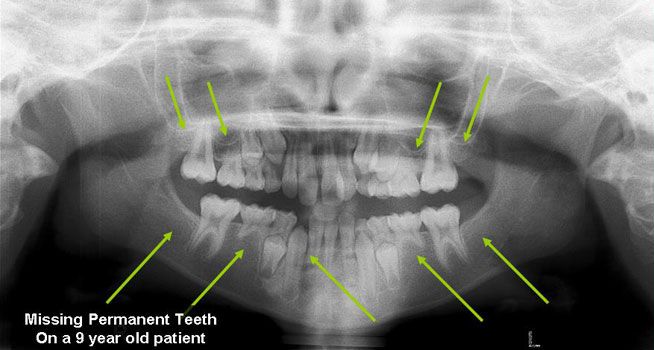

Missing Permanent Teeth

Hypodontia (the common dental term) describes a situation when fewer than 6 permanent teeth are missing, the term Oligodontia is used when more than 6 permanent teeth are missing (they were never formed). The most common missing teeth are the third molars (otherwise known as the Wisdom Teeth), followed by the premolars and the lateral incisors. Although it is not uncommon to have one missing tooth, patients with multiple missing teeth generally have a strong genetic component and it has been linked to conditions such as Ectodermal Dysplasia and several syndromes. Because early recognition aids in proper treatment, your dentist will refer you to specialists (orthodontist, oral surgeons, etc) that will determine which options suit you best to replace the missing teeth.